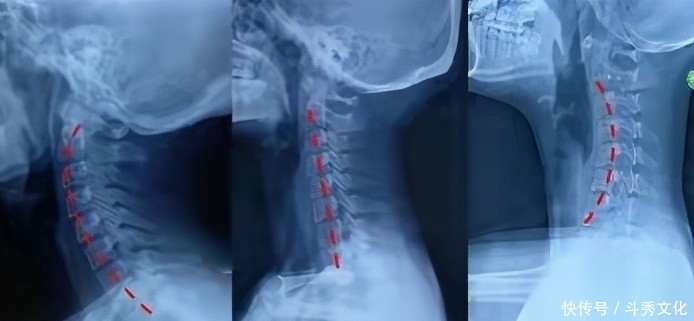

一旦颈椎发生生理曲度的变化,从正常的生理曲度前凸变为反弓或是直的状态,必然在颈椎4-5或是颈椎5-6之间出现明显的退变问题。

从而出现颈椎4-5、颈椎5-6之间的关节突关节错位紊乱、关节囊紧张或是炎症刺激压迫颈5神经、颈6神经。

在找出颈椎发生哪几个节段出现错位后,再分析它是往哪个方向的错位?如上图所示片子就可以分析出颈6椎体发生后下错位,而颈5椎体发生右侧偏移,颈4椎体也有后下错位;最后给予手法快速调整后,可以立竿见影起到缓解肩部疼痛的效果。